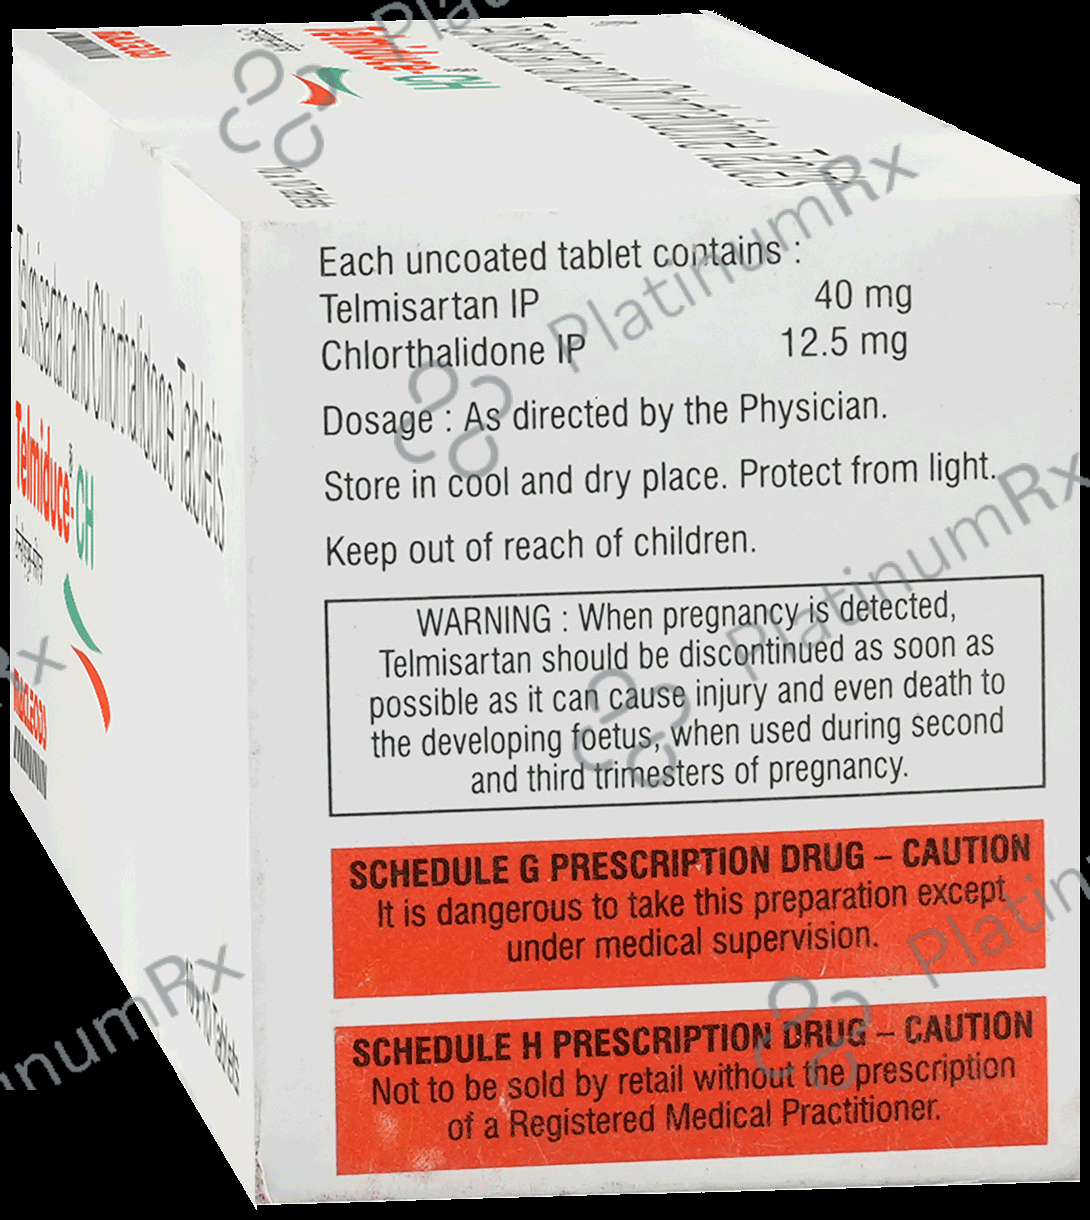

Chlorthalidone 12.5mg + Telmisartan 40mg

Salt CompositionChlorthalidone 12.5mg + Telmisartan 40mg (same for both)

Prescription Required

Telmiduce CH 40mg/12.5mg Tablet

Macleods Pharmaceuticals Pvt Ltd

Strip of 10 tablets

Telmiduce CH 40mg/12.5mg Tablet

Macleods Pharmaceuticals Pvt Ltd

Strip of 10 tablets

₹107.5

₹10.8 / Unit